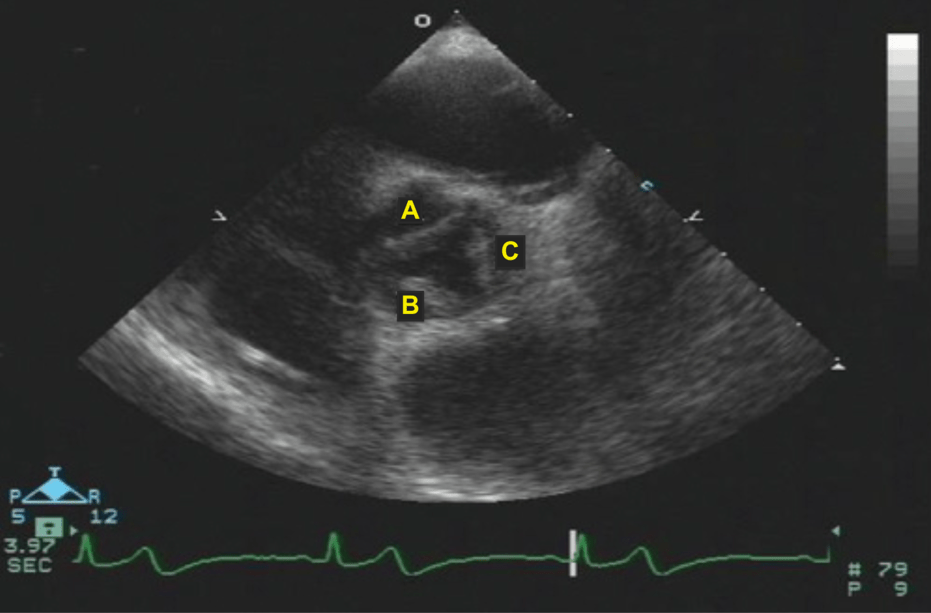

A 72 YOF presents with worsening dyspnea and severe MR with planned repair of the valve leaflet pictured. Which valve leaflet will be repaired?

Anterior leaflet (A1/2)

45 year old female presents for mitral valve replacement. Post induction the following image is obtained on TEE. What is the most probably cause of her mitral valve disease?

a. impaired production of connective tissue

b. calcification of the mitral valve commissures

c. myxoid infiltration

d. Aschoff nodules

"Billowing" of the mitral leaflets due to excess leaflet tissue characteristic of myxomatous mitral valve disease. Myxomatous degeneration refers to a pathological weakening of connective tissue characterized by myxoid infiltration.